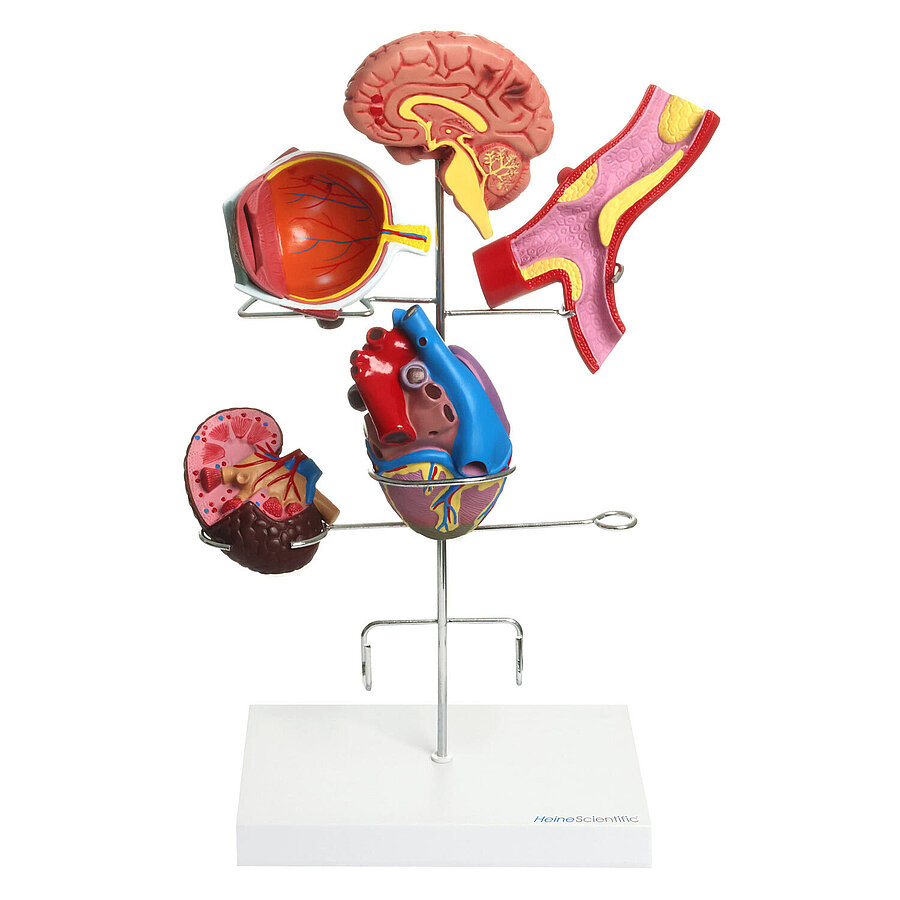

Modell der Hypertonie-Folgen

6-teilig, auf stabilem Gestell mit Kunststoff-Sockel

Zeigt die Folgeerkrankungen des Bluthochdrucks

Anatomische Strukturen sind aufwändig koloriert

Einzelne Organe bei Bedarf abnehmbar

Eignet sich perfekt zur Patientenaufklärung

Detaillierte Modelle für medizinische Ausbildungen

In unserem Sortiment finden Sie zahlreiche Modelle von HeineScientific sowohl für die Humanmedizin als auch für den Veterinärbereich. Hierzu zählen einzelne Körperteile, Organe, ganze Körperstrukturen oder Dentalmodelle. Mit ihrer Hilfe können Krankheiten und Funktionen nachvollzogen und gelehrt werden.